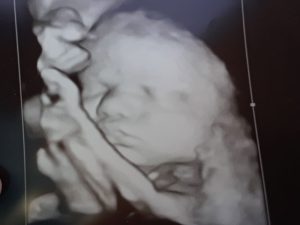

تفاوت جنین دختر و پسر در سونوگرافی

تفاوت جنین دختر و پسر در سونوگرافی چگونه تشخیص داده میشود؟ سونوگرافی نه تنها برای بررسی سلامت جنین به کار میرود، بلکه